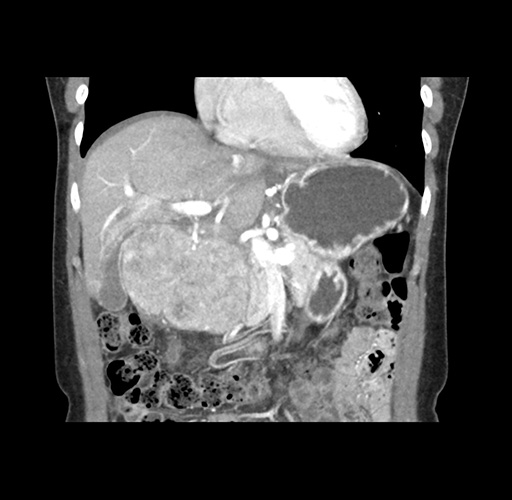

Imaging Analysis

Look through the patient's CT scan to identify any areas of concern for the necessary procedure.

Based on your CT findings, which issue(s) would give reason for "planned slowing down moment(s)" in this case?

Considering a standard left lateral sectionectomy procedure, what step(s) of the operation would you do differently in this case ?